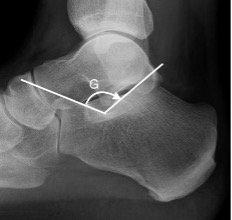

Bohler’s and Gissane's angles

G = Gissane angle

Between the downward (body and anterior calcaneal process) and upward (posterior articular facet) slopes of the superior calcaneal surface.

Normal: 120-145°